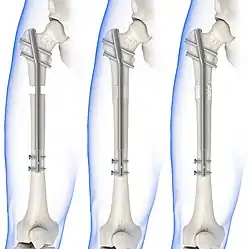

Internal fixators

Syndesmotic screws are the main, internal fixators used in surgeries for a Maisonneuve fracture. Two main types of syndesmotic screws are used: trans-syndesmotic screws (positioned at the level of the syndesmosis) and supra-syndesmotic screws (positioned above the syndesmosis).[14]

Based on several clinical results, syndesmotic screws are recommended to be fixed at least 1 centimetre proximal to the tibiofibular syndesmosis or 4 to 6 centimetres proximal to the tibiotalar joint line.[4][15] Cadaveric analyses, from a comparative study published in Foot & Ankle International in 1997, suggest that screw fixation at 2 centimetres proximal to the tibiotalar joint line is also adequate.[16] Biodegradable implants such as bioabsorbable screws, which do not require postoperative removal, may be used as an alternative to metallic hardware. However, biodegradable implants still limit rotation of the ankle and dorsiflexion of the foot.[4][6][13]

Following open-reduction, internal fixation is usually performed to stabilise the ankle mortise. To account for the distal fibula being slightly posterior to the distal tibia, drill holes are angled at 30° from the anteromedial aspect of the tibia to the posterolateral aspect of the fibula.[4][12][15] Trans-syndesmotic screws can be inserted in this way to ensure tibia fixation. Additional supra-syndesmotic screws may be temporarily inserted, for approximately 3 to 6 months, if instability is still present after fibular reduction. To reduce the fibula and restore the ankle mortise to its proper anatomical configuration, partial dorsiflexion of the foot is maintained prior to intraoperative screw fixation. This is because, in a neutral or maximally dorsiflexed position of the foot, the trochlear surface of the talus may reduce maximal postoperative dorsiflexion due to rigidity after screw fixation.[9][12]